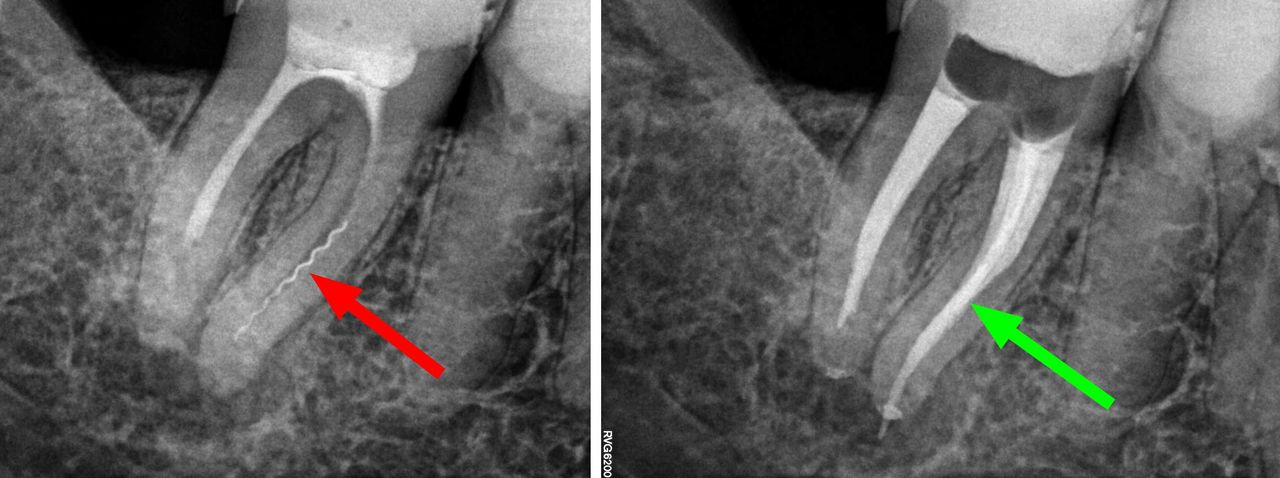

- Usuwanie złamanych narzędzi kanałowych oraz innych ciał obcych pozostawionych w kanałach korzeniowych

- Sterowana regeneracja uszkodzonych korzeni zębów stałych u dzieci na skutek urazów lub przewlekłych infekcji ropnych

- Specjalizujemy się w powtórnym leczeniu kanałowym i leczeniu powikłań co oznacza, że mamy wieloletnie doświadczenie w usuwaniu złamanych instrumentów kanałowych w szybki, bezbolesny i nieinwazyjny sposób. Dr Gończowski jest autorem specjalistycznego zestawu mikroinstrumentów (FRS®) przeznaczonych do usuwania ciał obcych z kanałów korzeniowych